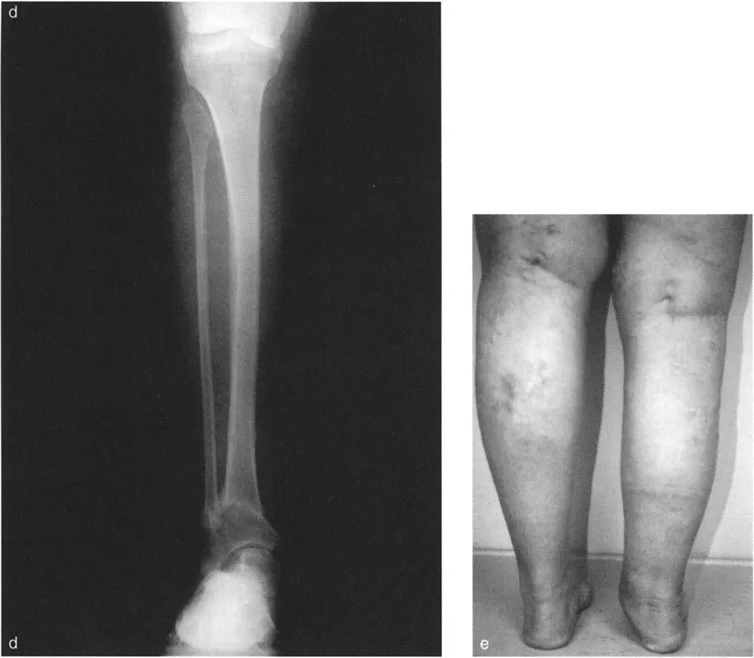

أنواع جراحات قطع العظم فوق الكاحل (Supramalleolar Osteotomy)

جراحة قطع العظم فوق الكاحل (SMO) هي الإجراء الأكثر شيوعًا لتصحيح تشوهات قصبة الساق البعيدة. تتضمن هذه الجراحة قطعًا دقيقًا في عظم الساق (القصبة) فوق مفصل الكاحل مباشرة، ثم إعادة محاذاة العظم وتثبيته في الوضع الصحيح. هناك عدة أنواع من هذه الجراحة:

2. قطع العظم الإسفيني المغلق (Closing Wedge Osteotomy):

• يتم إزالة قطعة صغيرة من العظم على شكل إسفين، ثم يتم تقريب أطراف العظم وربطها معًا.

• المميزات: يوفر استقرارًا عاليًا، ويسمح بالاتصال المباشر بين العظام، مما يسرع الالتئام ويسمح غالبًا بتحميل الوزن مبكرًا.

• العيوب: يؤدي إلى تقصير طفيف في الطرف، وهو ما قد لا يكون مرغوبًا في بعض الحالات.